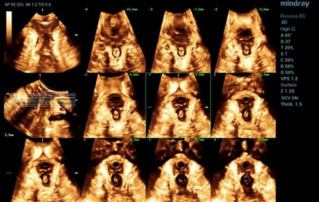

Female pelvic floor anatomy, which developed since the early 20th century, has had a variety of theories, including integral theory, three levels of vaginal support theory, "hammock hypothesis", and three-chamber system. Supporting structures such as pelvic floor muscles, fascia and ligament play an important role in maintaining the normal function of pelvic floor, among which levator ani muscle group is one of the most important supporting structures.